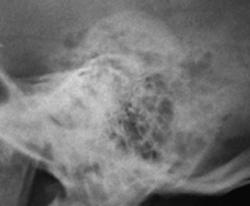

Иллюстрация 5 – произведена цифровая обработка изображения -  комментарии излишни.